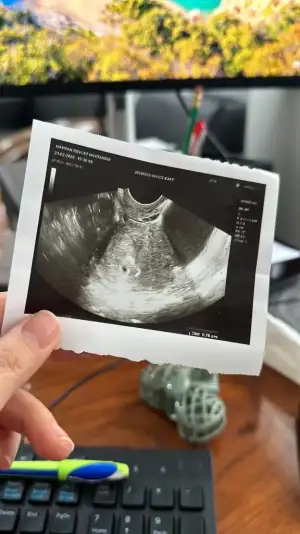

Merhaba, benim hamilelik testim de 21.02.2024 tarihinde iki çizgi çıktı. Hemen o gün yaptırdığım kan testinde de 805 olarak ölçüldü. Aile hekimi kadın doğuma yönlendirdi derken, geçtiğimiz cuma kesesi göründü. 10 gün sonra tekrar çağırdı. şuan sadece bekliyorum :) folik asit ve progestan ilaç verdi. geceleri bir kez fitil olarak alıyorum. Son adet gördüğüm tarih 25.01.2024. bebeğim kaç haftalık sizce ?

Merhaba, benim hamilelik testim de 21.02.2024 tarihinde iki çizgi çıktı. Hemen o gün yaptırdığım kan testinde de 805 olarak ölçüldü. Aile hekimi kadın doğuma yönlendirdi derken, geçtiğimiz cuma kesesi göründü. 10 gün sonra tekrar çağırdı. şuan sadece bekliyorum :) folik asit ve progestan ilaç verdi. geceleri bir kez fitil olarak alıyorum. Son adet gördüğüm tarih 25.02.2024. bebeğim kaç haftalık sizce ?